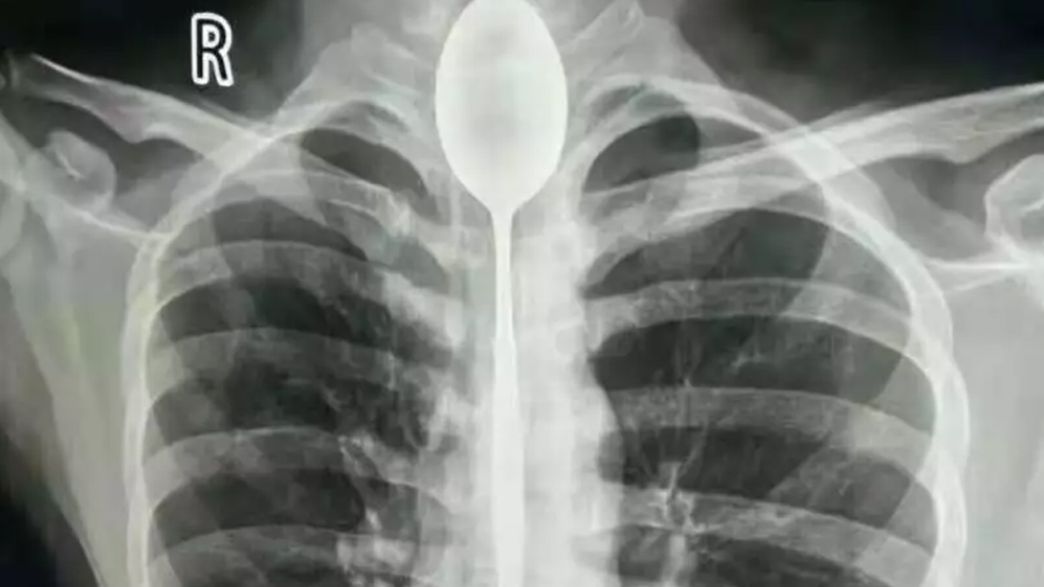

Doctors Extract Huge Spoon From Man S Throat A Whole Year After He Swallowed It